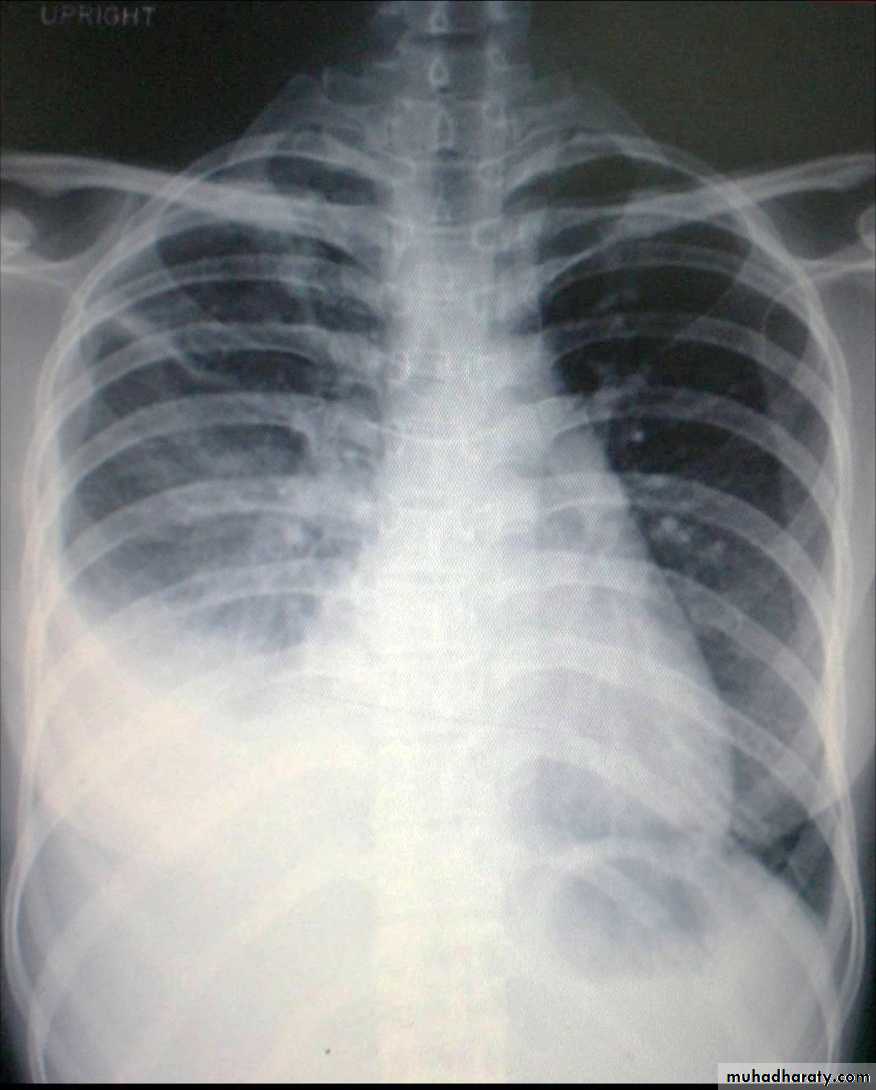

Chest X ray: The pleural fluid accumulates in the most dependent part of the thoracic cavity

The normally sharp posterior costophrenic angle is obliterated.

Upper surface is meniscus-shaped (meniscus sign).

Around 200 mL of fluid is required in order for it to be detectable

on a PA chest X-ray

The amount of pleural effusion may be small, large or massive.